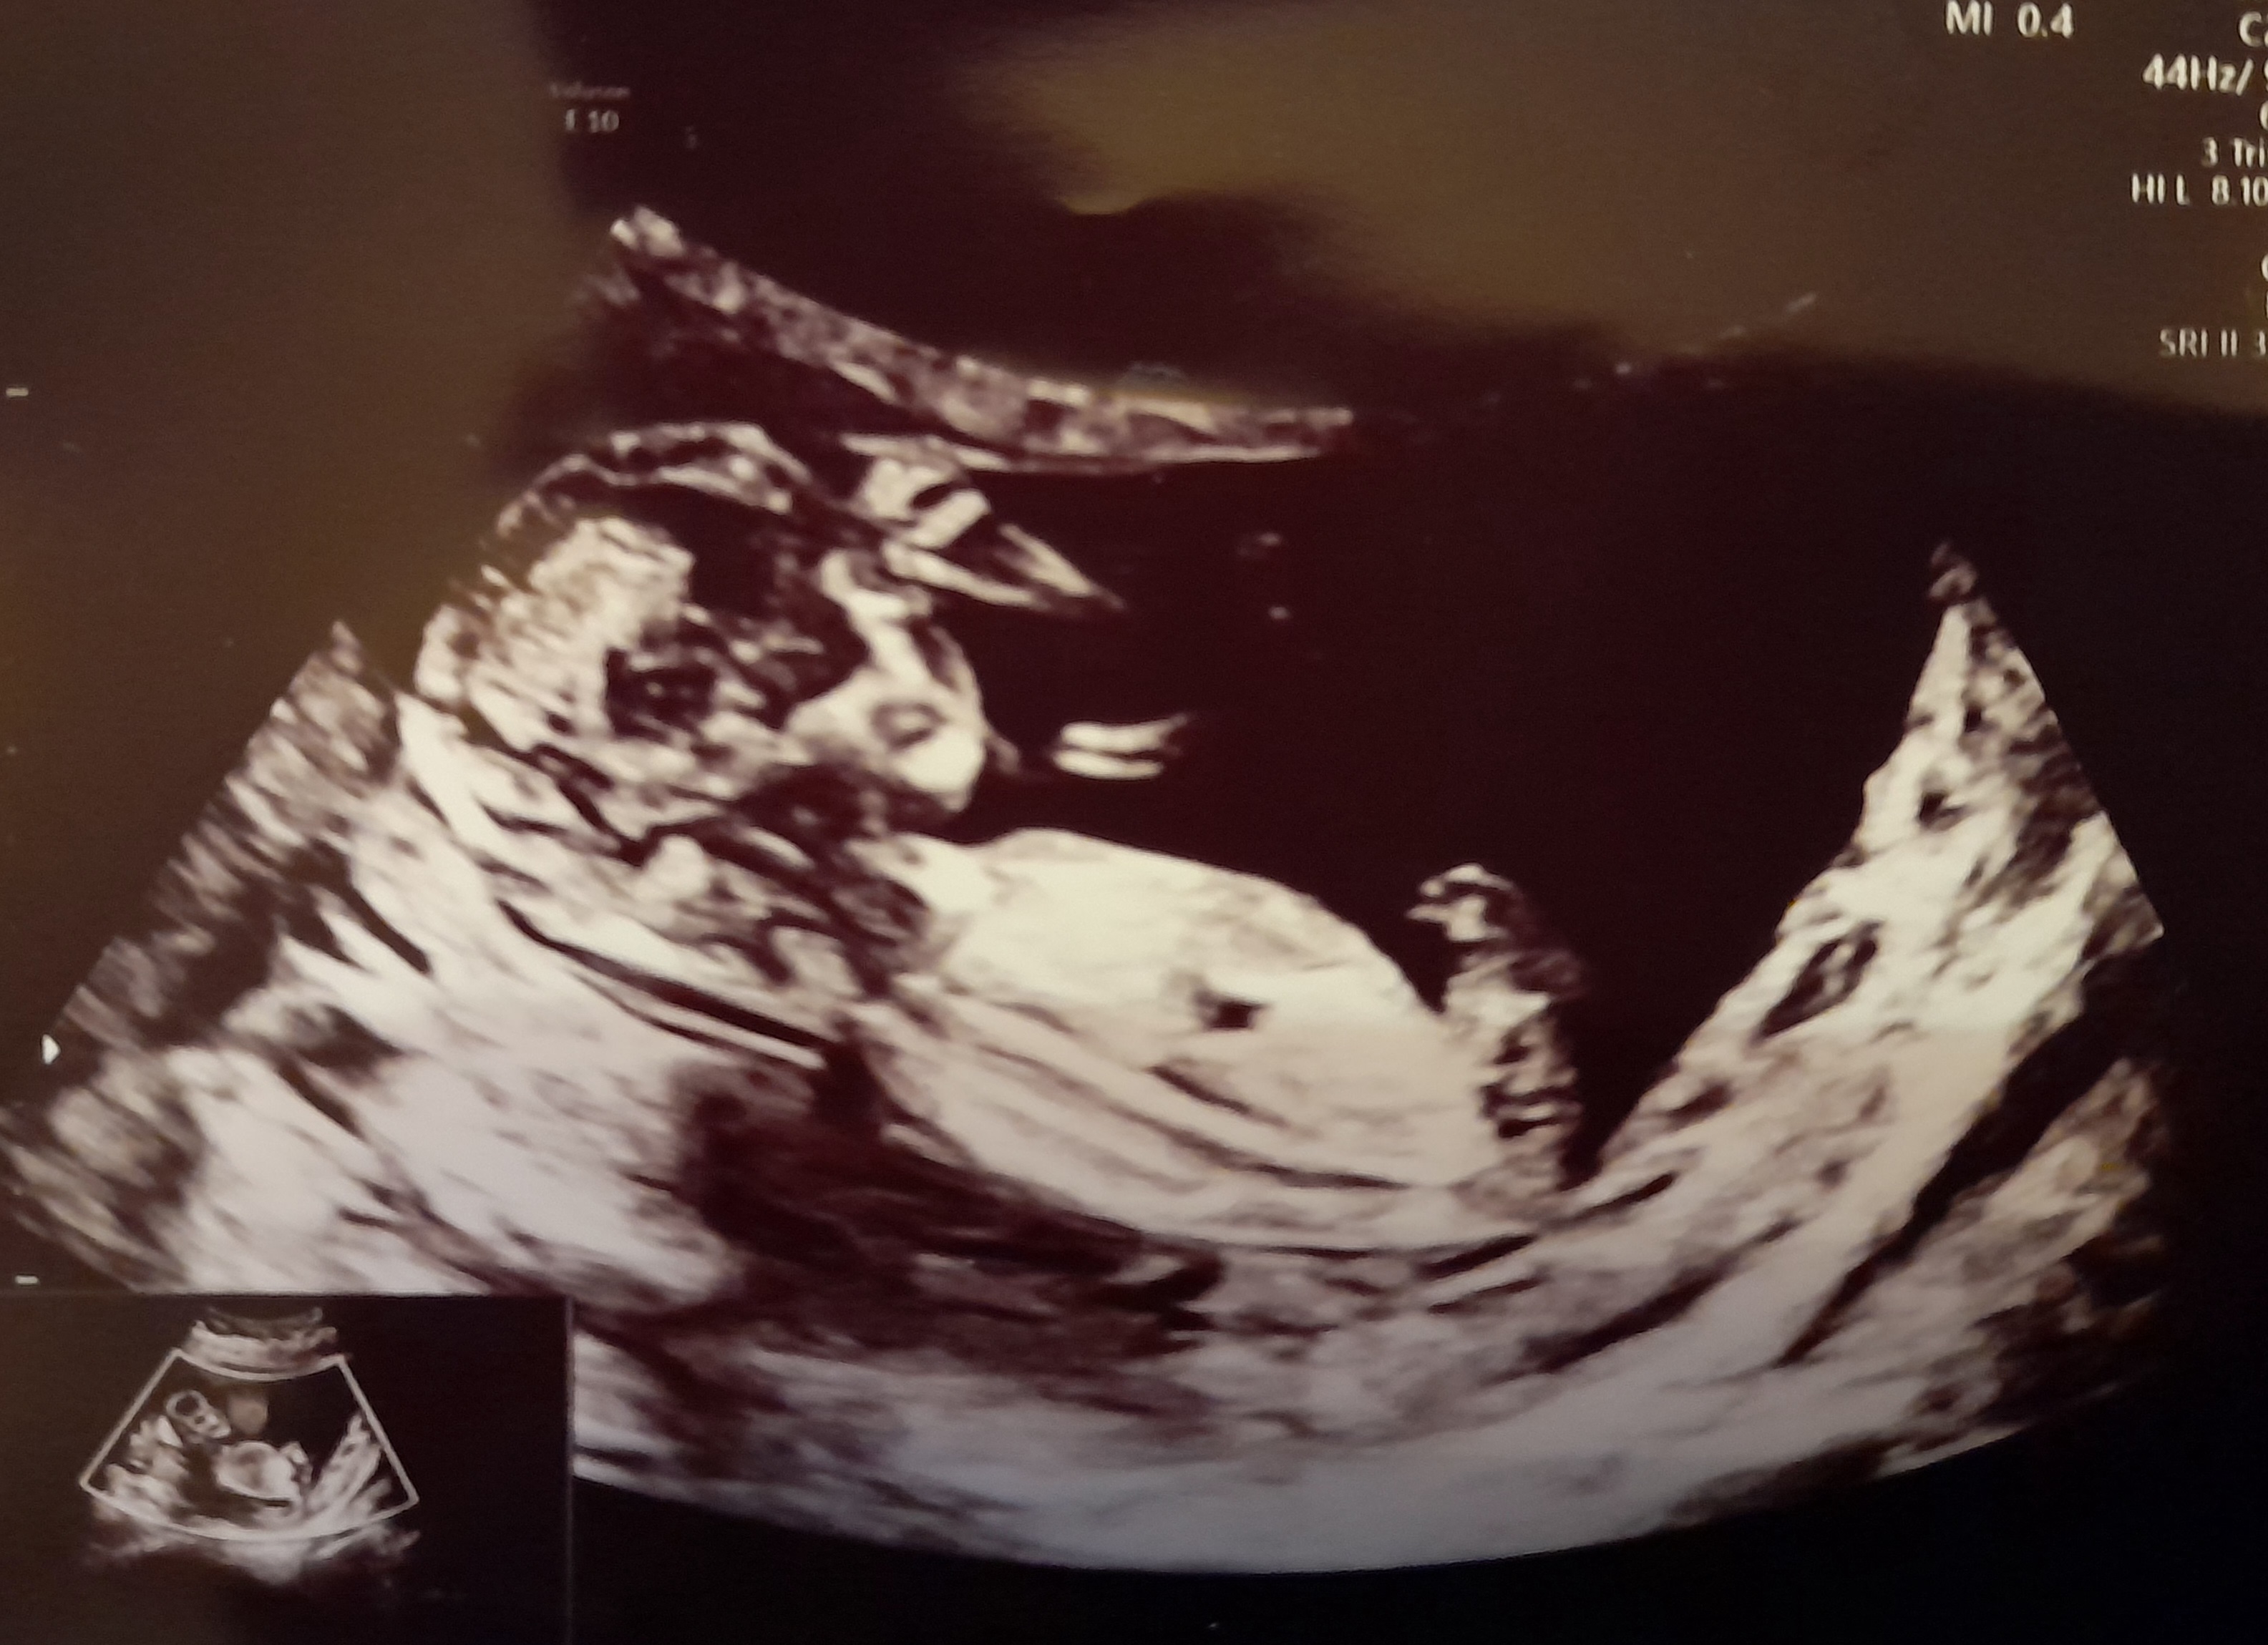

13+2

Tusen takk alle sammen❤️ Tankene deres hjalp masse på veien til sykehuset. Vi hadde time kl 10.00 og alt gikk bra!

Jeg holdt pusten omtrent da jordmor startet opp og fant Lille med en gang. Husbonden snufset litt og etterhvert som undersøkelsen skred fram og boks etter boks ble krysset av med 'normalt' så begynte tårene å renne hos meg og. Alt så fint ut og vi ble satt litt fram, fra 12+6 til 13+2.

Jeg spurte om kjønnet, men det mente JM det var for tidlig å se ennå. Tror ikke bildene viser noe, men et øyeblikk helt på slutten syntes jeg det så ut som nuben var veldig lett synlig så nå blir det spennende å se hva framtiden viser :joyful: :love017 ❤️